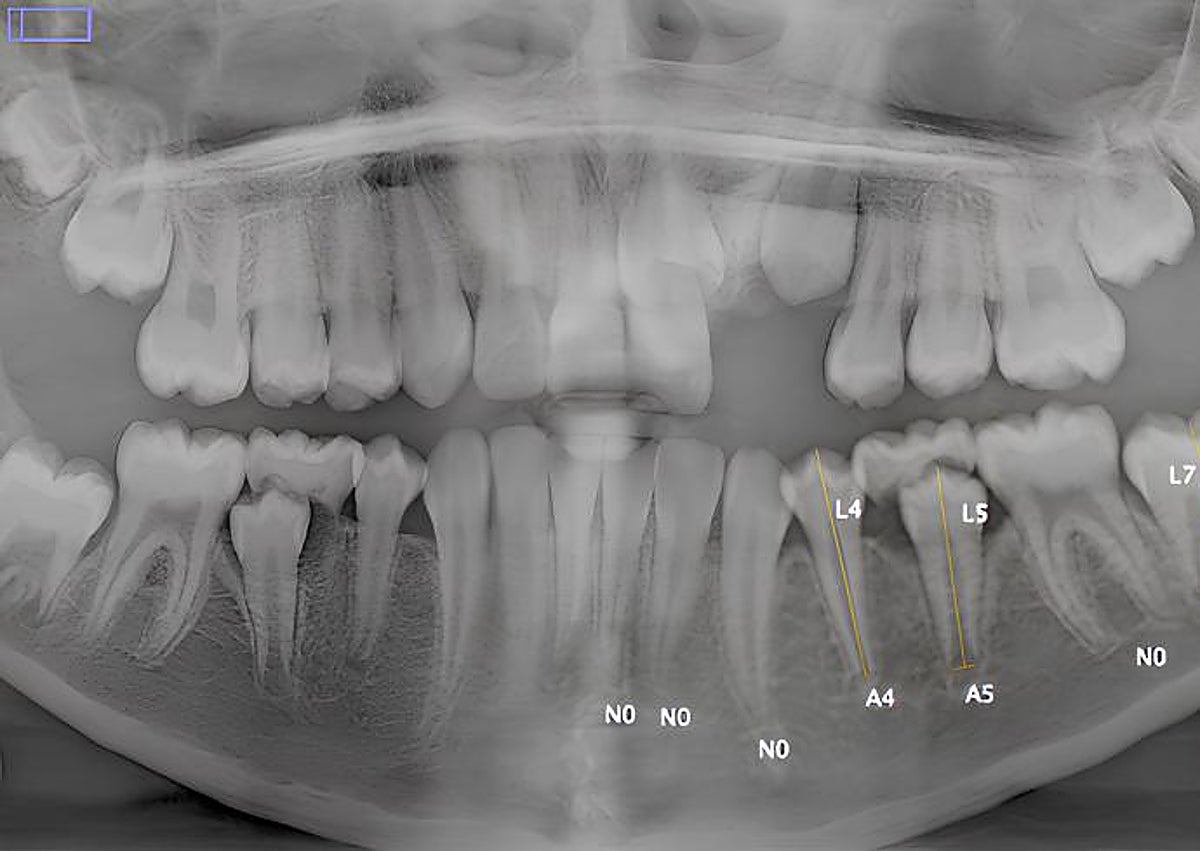

Los métodos que se usan para estimar la edad incluyen tres mediciones. La primera es un estudio dental. La segunda, el estudio de los huesos carpianos y las epífisis del cúbito y el radio. Y, la tercera, una combinación de ambos parámetros.

La colaboración con estos especialistas y profesionales ha permitido la recolección de una muestra de más de 15.000 radiografías de dientes, huesos de la mano y clavícula, cuyo análisis se ha llevado a cabo en estos últimos dos años en España, en conjunto con Panacea Cooperative Research S. Coop. Además, se han utilizado repositorios públicos de imágenes radiográficas. De Luca recuerda que el estudio radiográfico de los dientes, especialmente el tercer molar, de los huesos de la mano izquierda, y de la clavícula es muy útil para estimar, por ejemplo, la mayoría de edad, establecida en los 18 años por numerosos países.

Una de las publicaciones más recientes que se ha realizado en este marco hace referencia al estudio de una muestra poblacional procedente de Sudáfrica, de radiografías de los huesos de la mano y de los dientes que han permitido arrojar luz sobre la eficacia de una fórmula que los investigadores habían previamente desarrollado y validado exclusivamente en poblaciones europeas. Uno de los problemas con los que se encuentran estos estudios es la falta de pruebas forenses de menores africanos, asiáticos y latinos. Era necesario, para fines forenses, poder disponer de datos de poblaciones de esos lugares«. Así que uno de los autores de la investigación, que viajó como odontólogo voluntario a Sudáfrica, recopiló muestras. Y esos datos se han podido emplear ahora para validar los métodos de cálculo de la edad.